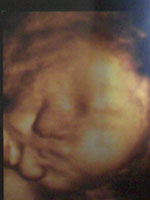

妊娠11ヶ月。 |

予定通りにいけば、今日が最後の健診日。 |

今日から、「正期産」に入りましたー。 |